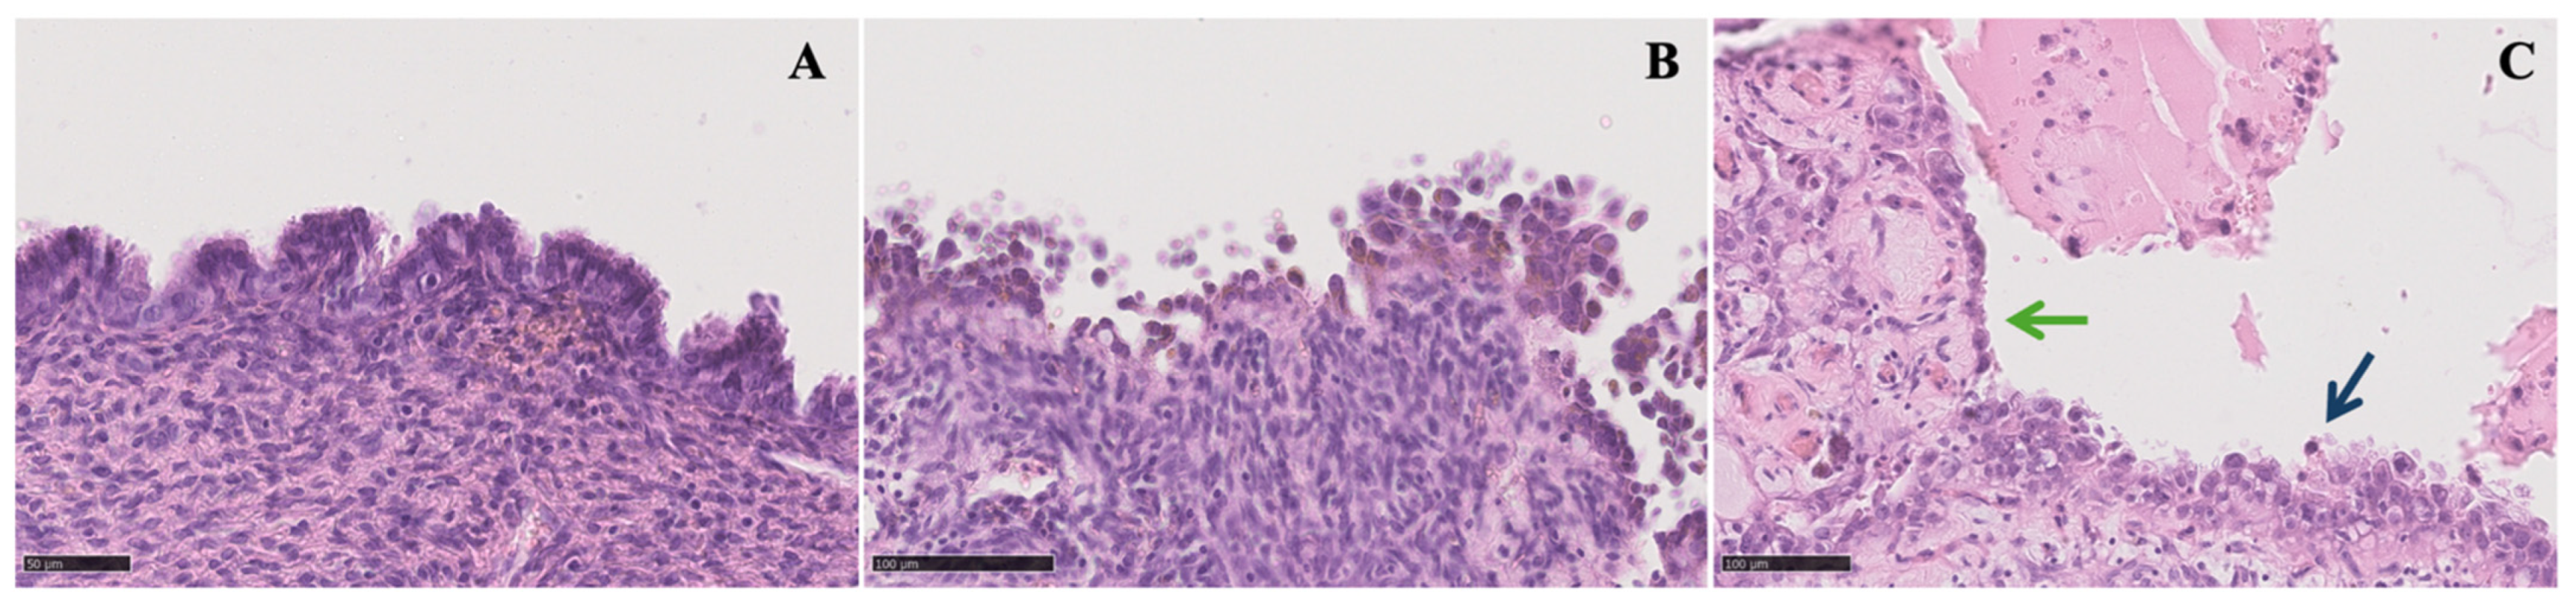

Figure 1.

Microscopic view of different grades of endometrioma atypia (50–100 μm): (A) typical endometrioma is lined by endometrioid epithelium with no endometrial stroma beneath it; (B) endometrioma with atypia showing nuclear pleomorphism, an inverted nucleus-to-cytoplasmatic ratio, and abundant eosinophilic cytoplasm with epithelial stratification and tufting; (C) endometrioma with foci of atypia (green arrow) and foci of clear cell carcinoma (blue arrow).